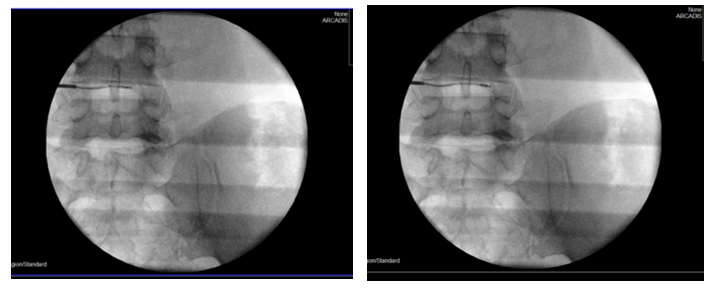

Με τον δεύτερο τρόπο γίνεται, υπό ακτινοσκοπικό έλεγχο, διαδερμική έγχυση ενός υλικού που έχει μορφή γέλης (gel) και συνίσταται από αιθανόλη, παράγωγα κυτταρίνης και ακτινοσκιερό υλικό tungsten (σχ.3). Η έγχυση γίνεται στο κέντρο του δίσκου, μέσα από έναν οδηγό και λειτουργεί άμεσα. Η δράση του διαλύματος στηρίζεται στις φυσικοχημικές ιδιότητές του: απορροφητική επίδραση της αιθανόλης με το νερό, που περιέχεται στον δίσκο, σε συνδυασμό με ένα φαινόμενο ώσμωσης- αφυδάτωσης του δίσκου από την περιφέρειά του προς τον πυρήνα του. Έτσι, «απορροφάται» η προβολή του δίσκου πίσω προς το κέντρο του (σχ.4).

Περίπτωση 2: Ακτινοσκόπηση σε Διαδερμική Δισκοπλαστική με χρήση ενδοδισκικού υλικού Discogel σε κήλη μεσοσπονδυλίου δίσκου Ο4-Ο5.